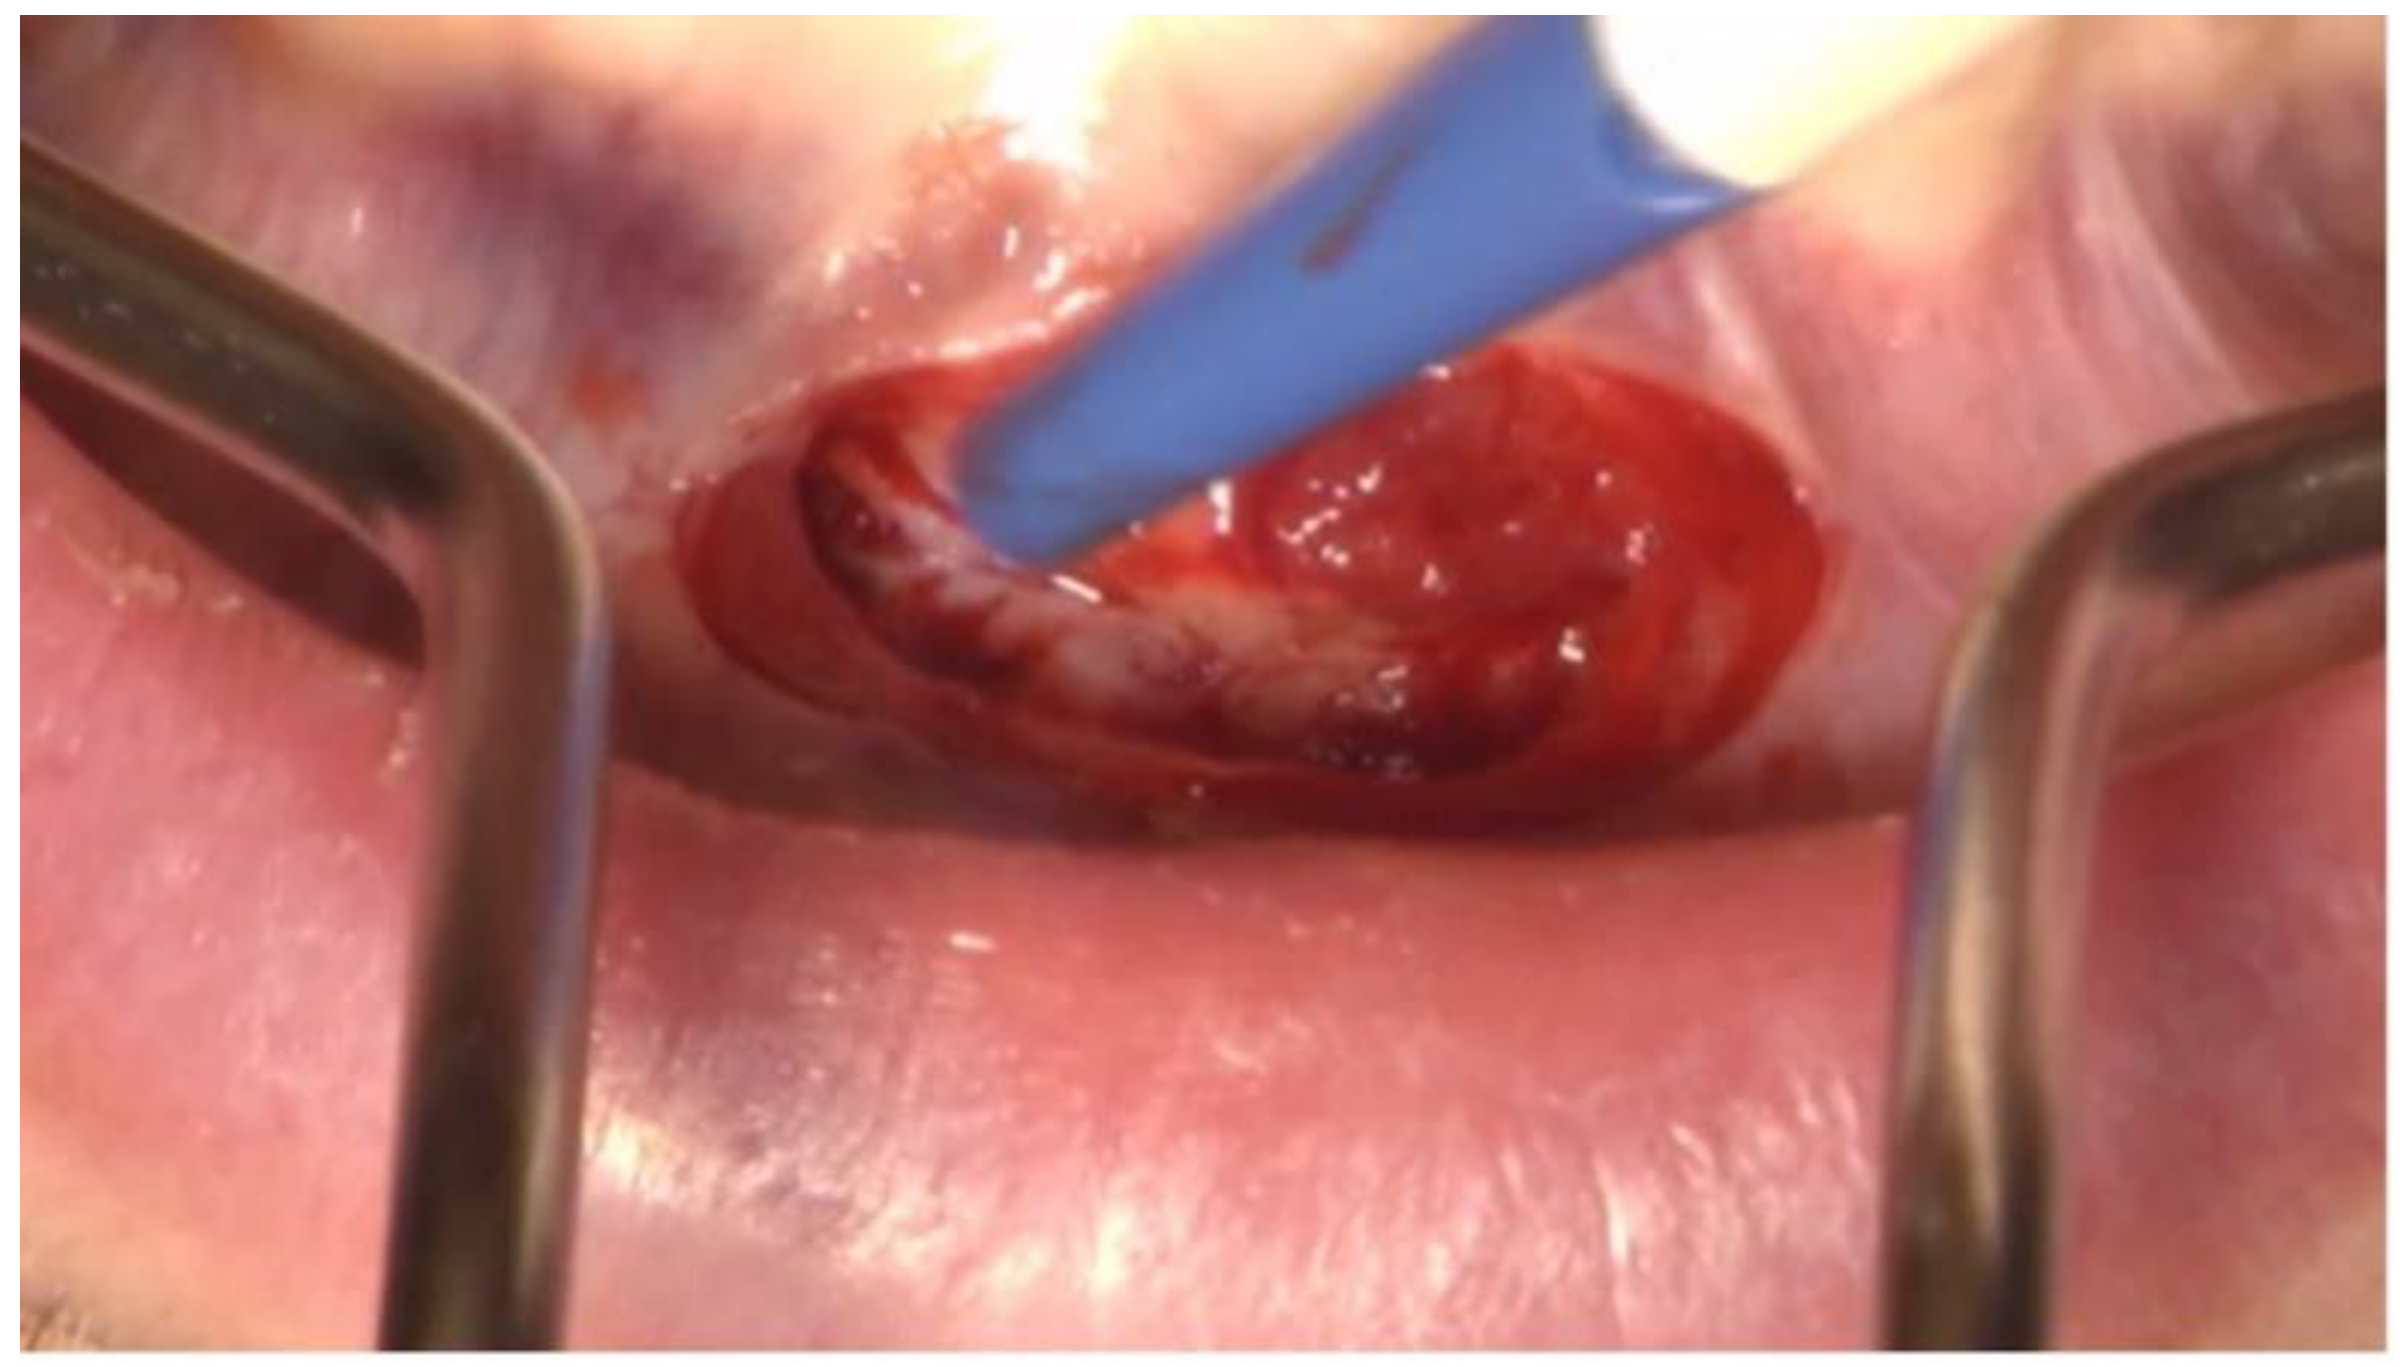

3. Clinical Procedure and Outcome